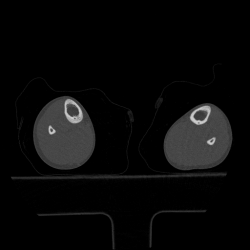

Мальчик 8 лет, был направлен травматологом к нам, с жалобами: на ноющую боль в голени в течении 2 мес., преимущественно усиливающася в ночное время, но проходящая после приёма НПВС. Провели МСКТ:

Думаю, что большого труда не составит определиться, что это за патологическое состояние, хоть и был отход от "классики". Случай ещё пока не верифицирован!

Остеоид-остеома. А в чем отход от классики?

Диф.ДЗ с первично-хроническим остеомиелитом.

Интересное наблюдение, но для "классики" остеоид - остеомы не хватает - пуговки - подобия секвестра в полости, но это в любом случае хронический остеомиелит подлежащий оперативному лечению.